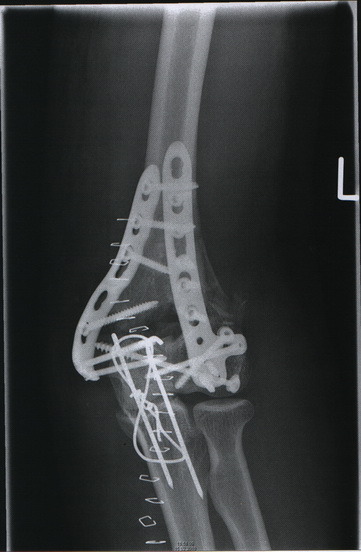

dann will ich in dem Fotothread auch mal mitmachen...

Willkommen im Titan lager...

bei mir wars am 13.2. beim Langlauf....Huuuussstt.....also ohne XT....

2010-02-19 10-32-09_0020a.jpg

2010-02-19 10-29-07_0019a.jpg

Georg, bei dir im Skelett sieht´s ja aus wie die bunte Mischung in der Werkstattwühlkiste :wink: